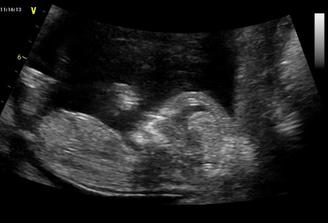

Katy+Naty

Tak se nám poštěstilo a s milovaným jsme počali dvojčátka, která by měla přijít na svět začátkem dubna, ale myslím, že to bude dřív, jak to u dvojek bývá. Pan Dr. nám potvrdil ve 20.tt, že to budou slečny🙂